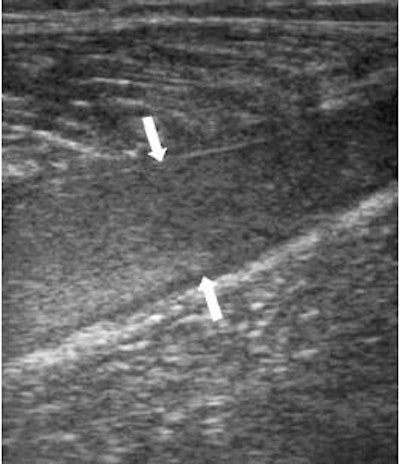

![]() |

| Same patient as above. The longitudinal image four weeks later shows the reparative process as a hypoechoic area (arrows) and a well-defined anechoic fluid collection. Kwak H, Han Y, Lee S, Kim K, Chung G, "Diagnosis and Follow-up US Evaluation of Ruptures of Medial Head of the Gastrocnemius ('Tennis Leg')," Korean J Radiol 7(3), September 2006. |